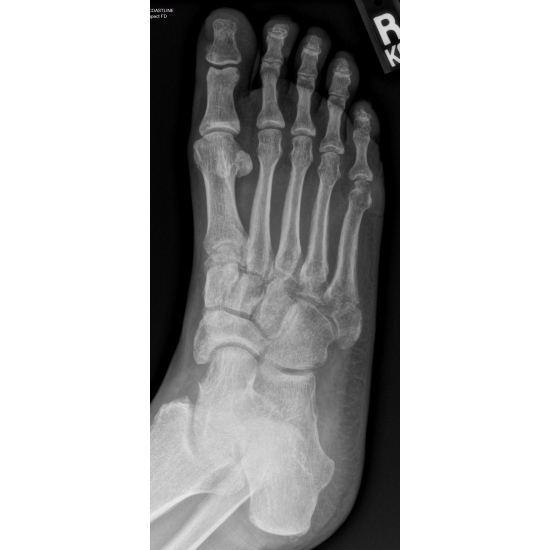

She continued with protected weight bearing in a walking boot and was later placed in a non-weight bearing cast for 4 weeks because of increasing diastasis of her fracture pieces. Case Photo #3 Case Photo #4